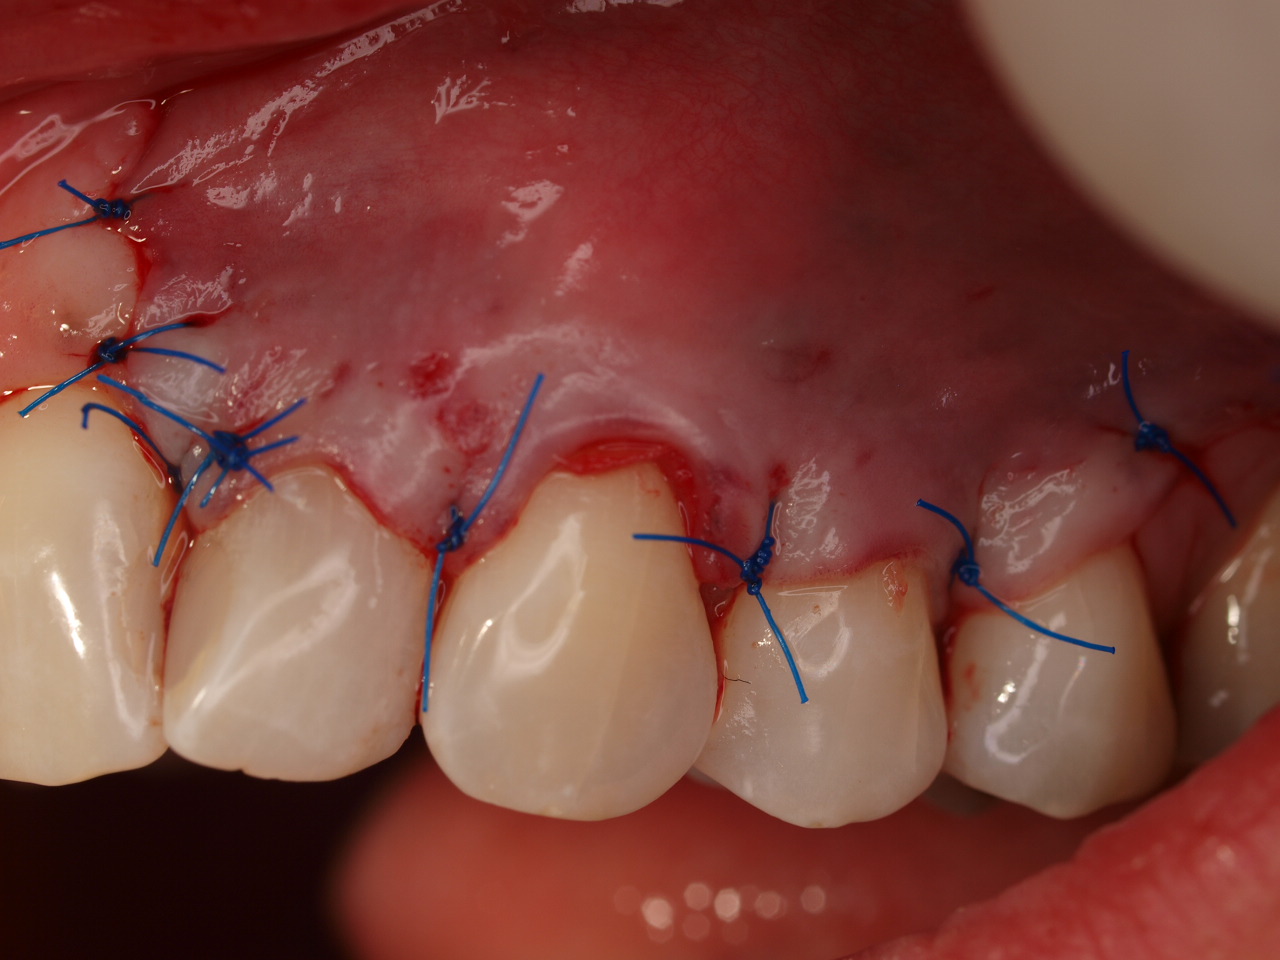

Multiple gingival recessions treated by MCAT with mucoderm® and Straumann® Emdogain® (2) - Rathe

Pre-operative clinical situation. Shallow multiple adjacent gingival recessions in the first quadrant.